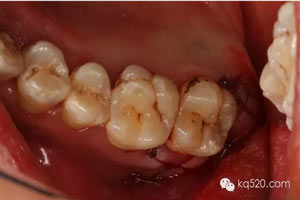

圖3.全景片影像檢查:28牙根似乎位于上頜竇內(nèi),拔除28要注意上頜竇瘺。

圖8.去骨后,可見28的牙冠,牙冠合面朝向遠中水平。

徹底暴露28的牙冠和牙根。